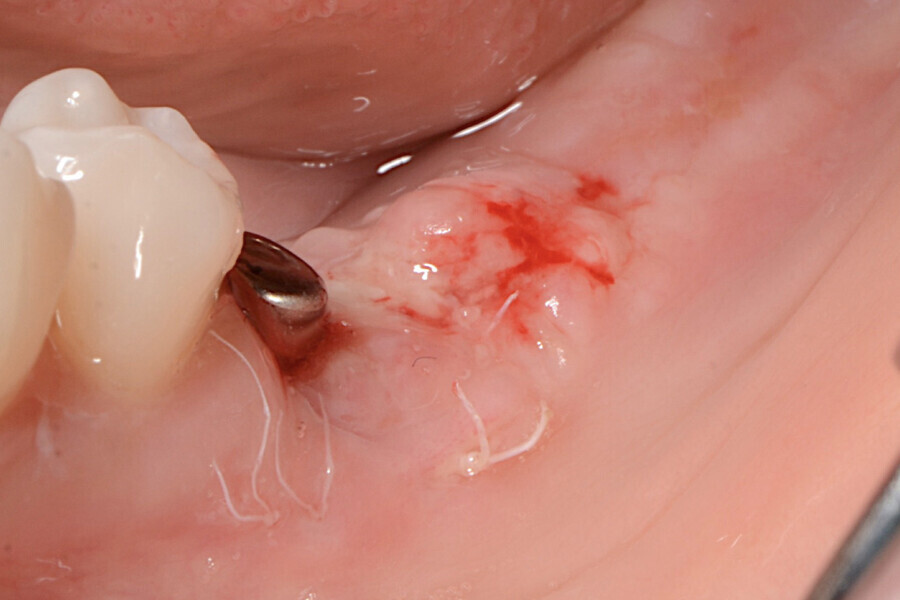

La zone opératoire a été anesthésiée avec de l’articaïne et de l’épinéphrine à 1:100 000. Le site receveur a été incisé au moyen d’un scalpel tranchant, afin de créer un lit périosté libre de toute attache musculaire. Deux incisions crestales parallèles ont été effectuées au niveau de la région distale des implants avec une lame n° 15C, et reliées par une incision horizontale (Figs. 2 à 5).

Le prolongement des incisions vers la région crestale et la distance qui les sépare, dépendent du volume de la greffe de tissu kératinisé nécessaire pour chaque cas. La désépithélialisation du lambeau a été effectuée à l’aide d’une lame n° 15C (Fig. 6), et un lambeau d’épaisseur partielle a été élevé (Fig. 7). Le lambeau a été décollé par une incision superficielle interne de la partie apicale, afin d’en permettre le déplacement passif et la suture sans tension. Le lambeau a alors été déplacé en direction mésiale avec une rotation de 180° (Figs. 8 et 9).

Figs. 6-9 : Lambeau d’épaisseur partielle.

La papille mésiale a été préparée pour une greffe par une technique de tunnelisation (Fig. 10). Le lambeau obtenu a été suturé à la base du vestibule fraîchement créé du site receveur, au moyen d’un fil en PTFE non résorbable no 5/0 (Coreflon, IMPLACORE). Le greffon a été roulé à l’intérieur du rebord gingival et fixé en mésial, par des fils de sutures en PTFE (Figs. 11 à 14).